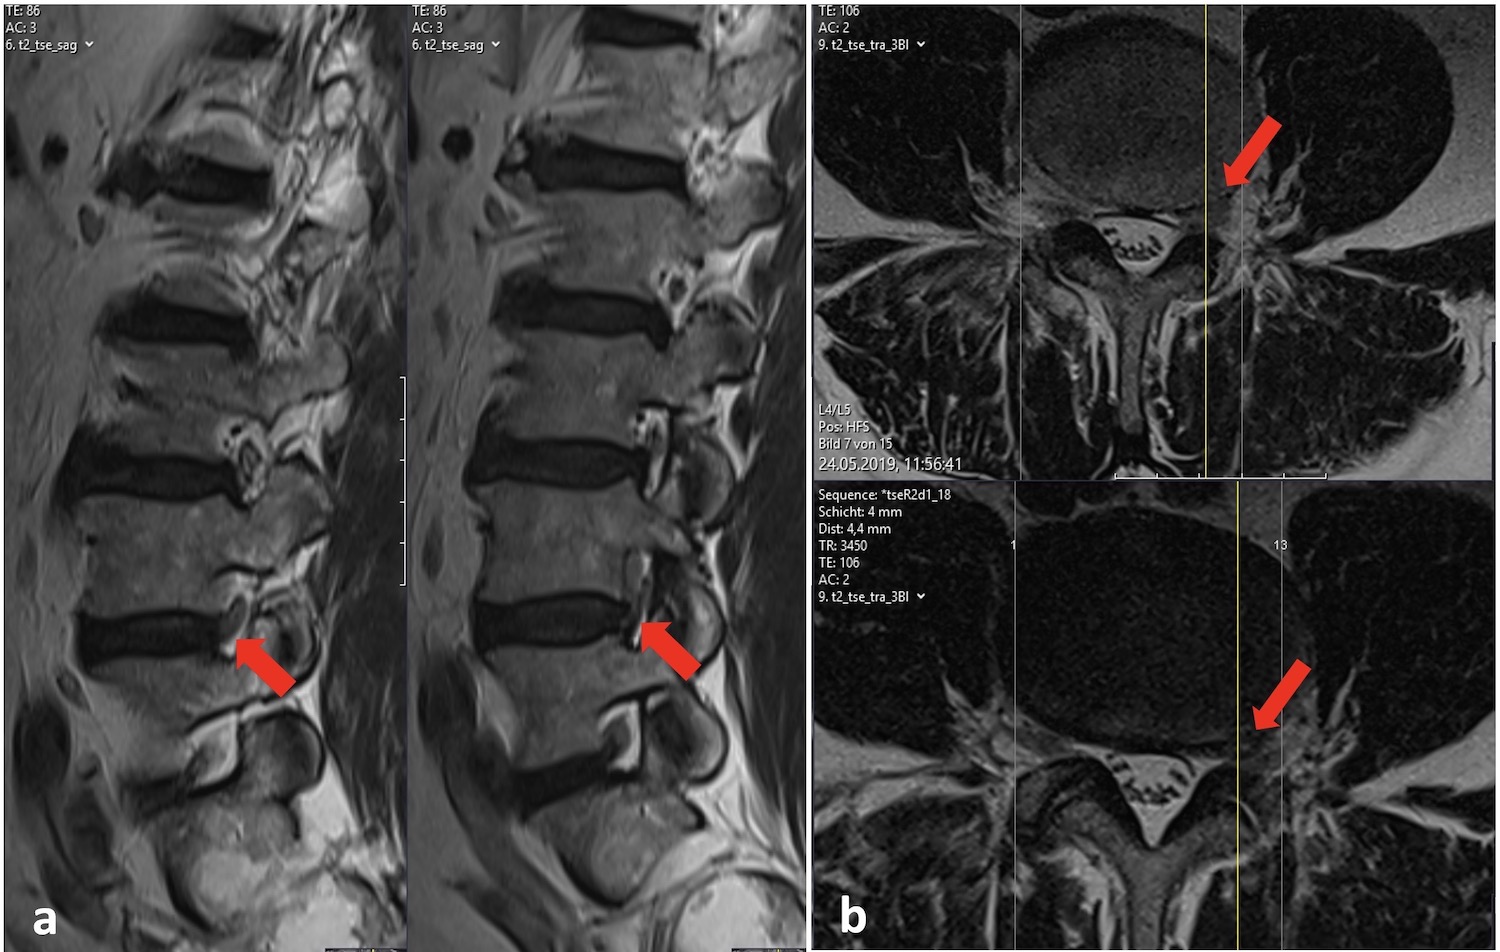

Bandscheibenvorfall an der Lendenwirbelsäule Dr. Burkhardt (Hirslanden)